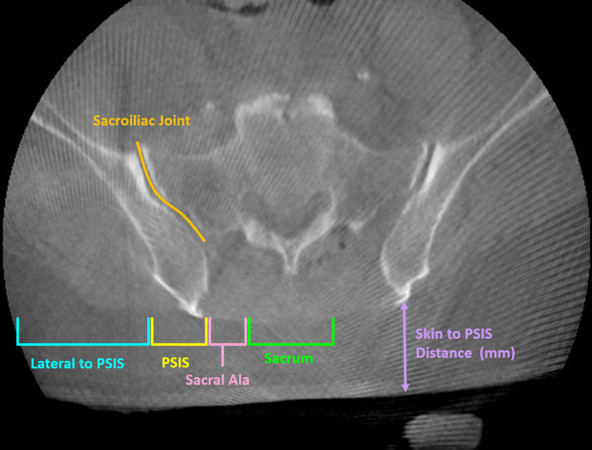

Methods: This is a single-centre, institutional board approved, multisurgeon retrospective analysis of 69 included DRB placements from 51 robot-assisted lumbar posterior instrumentation procedures between May 2022 and April 2024. Pin entry point and trajectory were mapped out; the intraoperative O-arm CT scans and skin-to-PSIS depth were also measured, and patient demographics (age, sex, BMI), surgical outcomes, and postoperative complications were recorded.

Results: Of the 69 PSIS pin placements, 47 (68.1%) had the correct entry point on the PSIS, and 35 (50.7%) of them were placed correctly within the ilium without breaching a second cortex. Skin-to-PSIS depth was significantly higher in patients with misplaced DRB placement, while age, sex, and BMI were similar. Of those with misplaced DRB (n = 34), one had delayed pin site wound healing.

Conclusion: Percutaneous PSIS DRB placement has poor accuracy, with skin-to-PSIS depth being a significant factor. To avoid complications from misplaced DRB placement, the authors recommend the use of DRB placement on the iliac wing, or on the PSIS, following the trajectory used in pelvis posterior column fracture fixation, using fluoroscopy intraoperatively to ensure the DRB pin position.